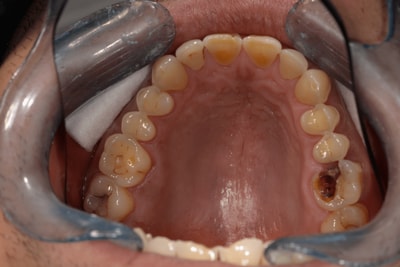

Lorsqu’une carie est très étendue et qu’une réparation classique par composite ou amalgame est impossible, nous vous conseillons la réalisation d’un inlay ou d’un onlay. Il s’agit d’un dispositif « sur mesure », réalisé par notre prothésiste. Il est donc exactement adapté à la cavité, à la dent support, aux dents controlatérales , ainsi qu’aux antagonistes. Il présente des propriétés bio-mécaniques comparables à celles d’une dent saine. Il est une excellente alternative à une couronne lorsque la dent le permet. Il est fixé à la dent par collage (protocole rigoureux permettant à la dent de rester étanche).

L’inlay-onlay s’impose aujourd’hui comme la technique de restauration la plus sûre, et offre les meilleures perspectives d’avenir à vos dents. La résistance mécanique des inlays et des onlays est bien meilleure que celle des plombages dentaires et des résines réalisés directement au cabinet par les techniques classiques. Par ailleurs, les inlays et les onlays permettent d’obtenir un joint de meilleure qualité qu’avec une obturation classique. On augmente ainsi la fiabilité du point de contact avec les dents adjacentes, ce qui permet de réduire le risque de reprise de carie et les problèmes d’inflammation gingivale. Dans le cas de caries de volume important, la réalisation d’un inlay ou d’un onlay permet souvent d’éviter de réaliser une couronne dentaire qui entraînerait un délabrement plus important de votre dent.